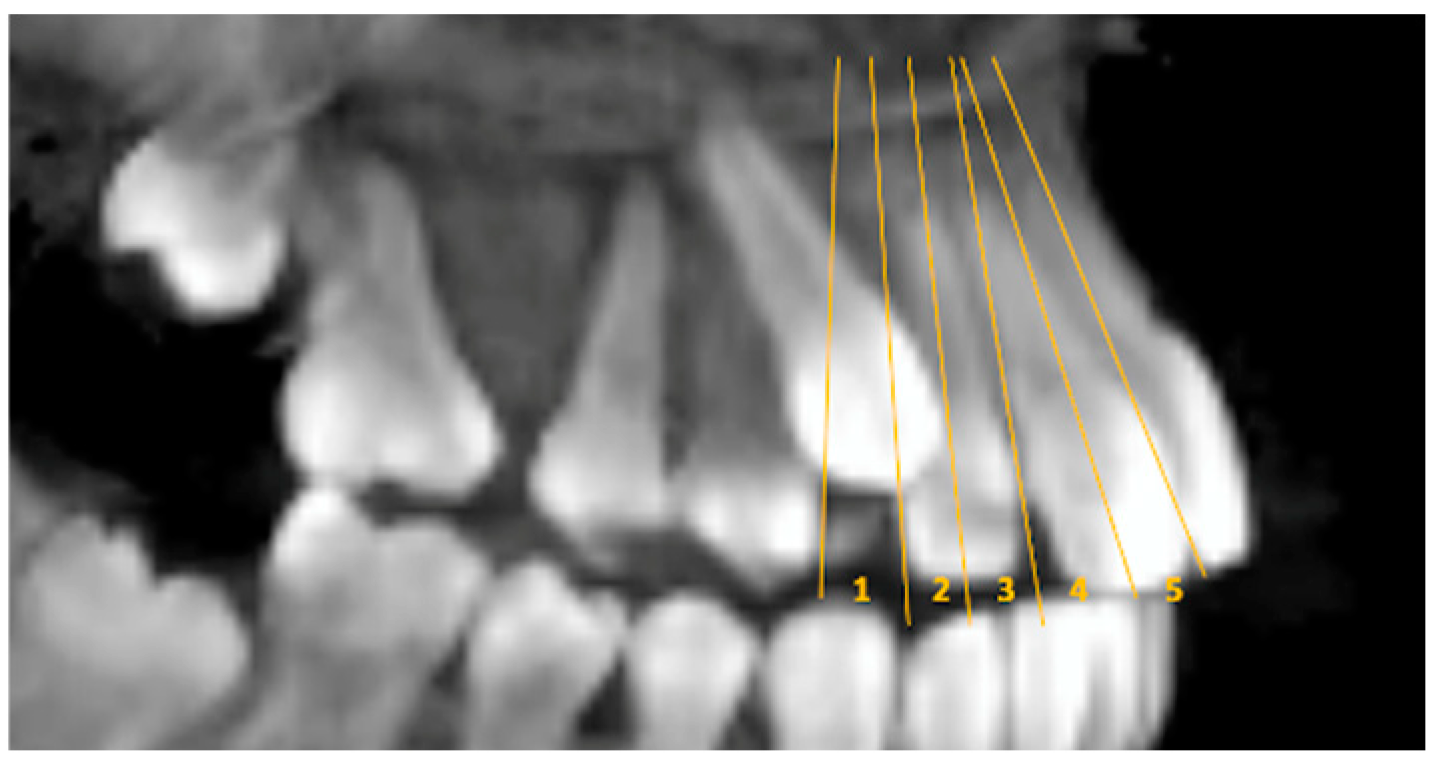

Sector; sagittal view illustrating reference lines of canine overlap (sectors) assigned to one of five categories: 1 = normal position; 2 = distal to the long axis of the lateral incisor; 3 = mesial to the long axis of the lateral incisor; 4 = distal to the long axis of the central incisor; 5 = mesial to the long axis of the central incisor [19] (p. 13) (Figure 2).

Figure 2. Sagittal view illustrating reference lines of canine overlap (sectors) assigned to one of five categories.